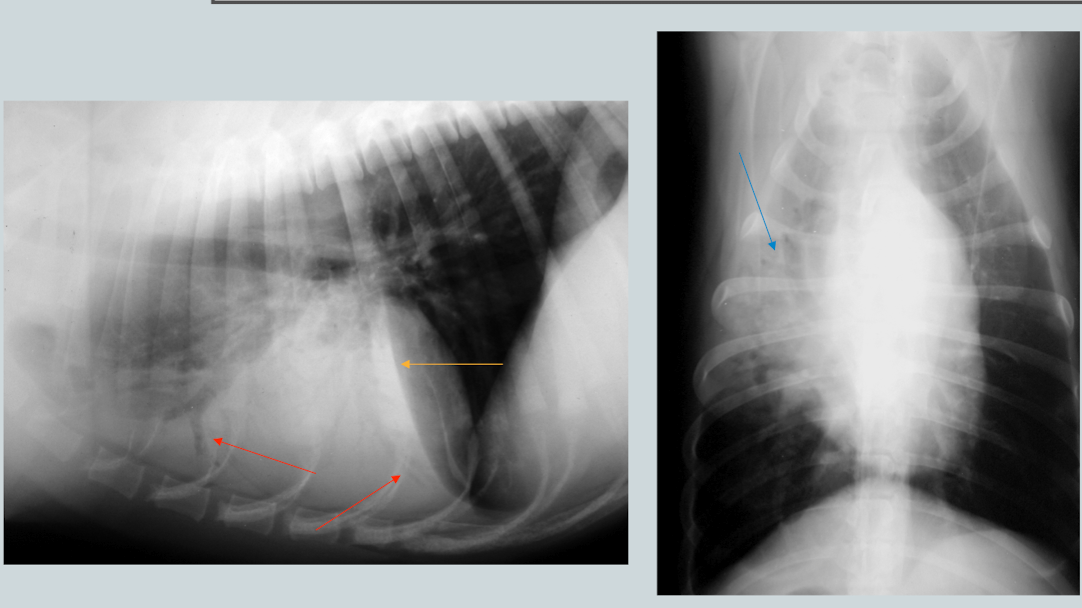

What is the likely condition? What are the arrows pointing to?

Aspiration pneumonia (bc right middle)

red: air bronchogram

blue: border effacement

yellow: lobar sign